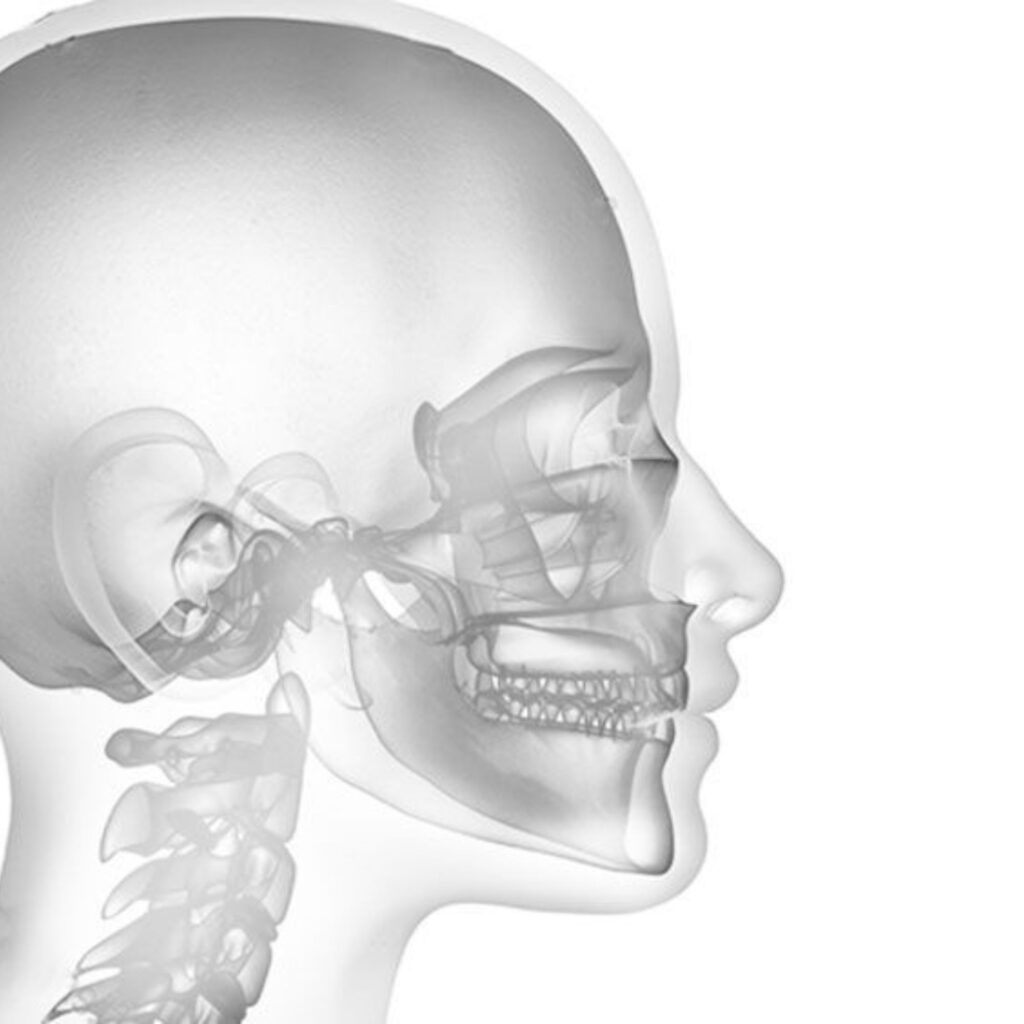

La chirurgie orthodontique, aussi appelée chirurgie orthognathique, est envisagée lorsque des désalignements dentaires et maxillaires ne peuvent être corrigés uniquement avec des appareils orthodontiques. Ces interventions sont souvent recommandées pour améliorer la fonctionnalité, l’esthétique du visage, et la qualité de vie.

- Ostéotomie mandibulaire : Réalignement de la mâchoire inférieure.

- Ostéotomie maxillaire : Réalignement de la mâchoire supérieure.